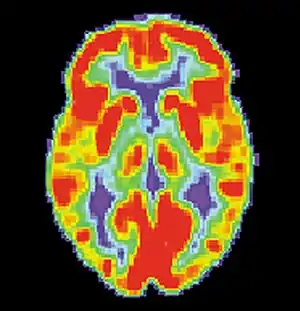

A follow-up to the previous research was conducted by Daniel L. Schacter and colleagues. Similar to the study by Henry L. Roediger and Kathleen McDermott, subjects were read a list of associated words before they went into the PET scanner. During the first scan, subjects would make recognition judgments to determine what were the previous presented words.[2] During the second scan, subjects had to make judgments about words that were not presented. For example: bed, rest, dream, tired, and awake would be in the list but not the word "sleep". As with the study by Henry L. Roediger and Kathleen McDermott, subjects claimed to remember similar amounts of non-presented words as they did the words that were actually presented.[2] The researchers noted that brain activity during the true and false recognition tasks were very similar. Monitoring the blood flow in the brain revealed there were in the left medial temporal lobe for both veridical and illusory recognition.[17]

That is not to say that there were not differences. While monitoring blood flow in the brain during false recognition, a part of the frontal lobe that is thought to be a key monitor of memories actually showed greater activity when presented with a false recognition than with a true one.[2] There seemed to be some discrepancy as subjects attempted to scrutinize the out-placed words, but were overcome by powerful memory illusion.[2] This study demonstrates the ability of technology to help researchers understand to a greater extent the power of false memories.